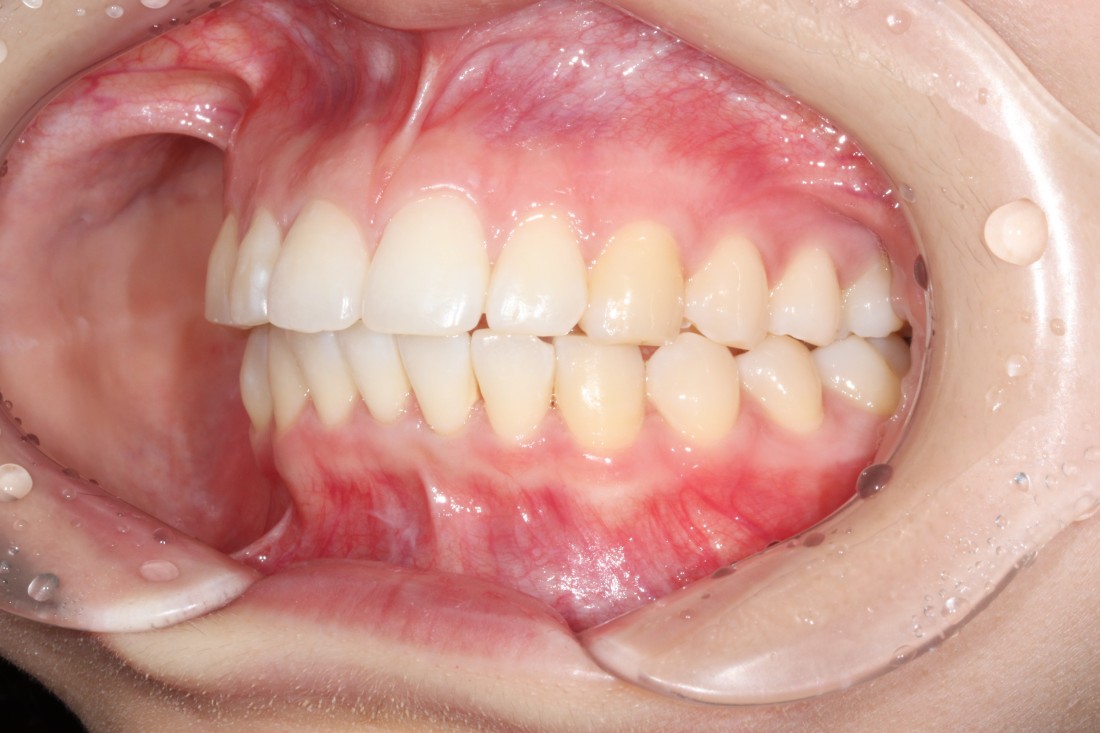

광주 교정치과

충치치료 + 치아교정 동시 케이스

광주 교정치과 추천하는 이유는

전문의 충치치료까지 동시에 가능하여

토탈 구강건강 관리를 받으실 수 있기 때문입니다.

5층은 일반진료센터,

4층은 VIP 치아교정실로 운영되어

치아교정 진료만을 담당하는

교정전담 의료진의 세심한 케어로

광주 교정치과를 추천합니다.